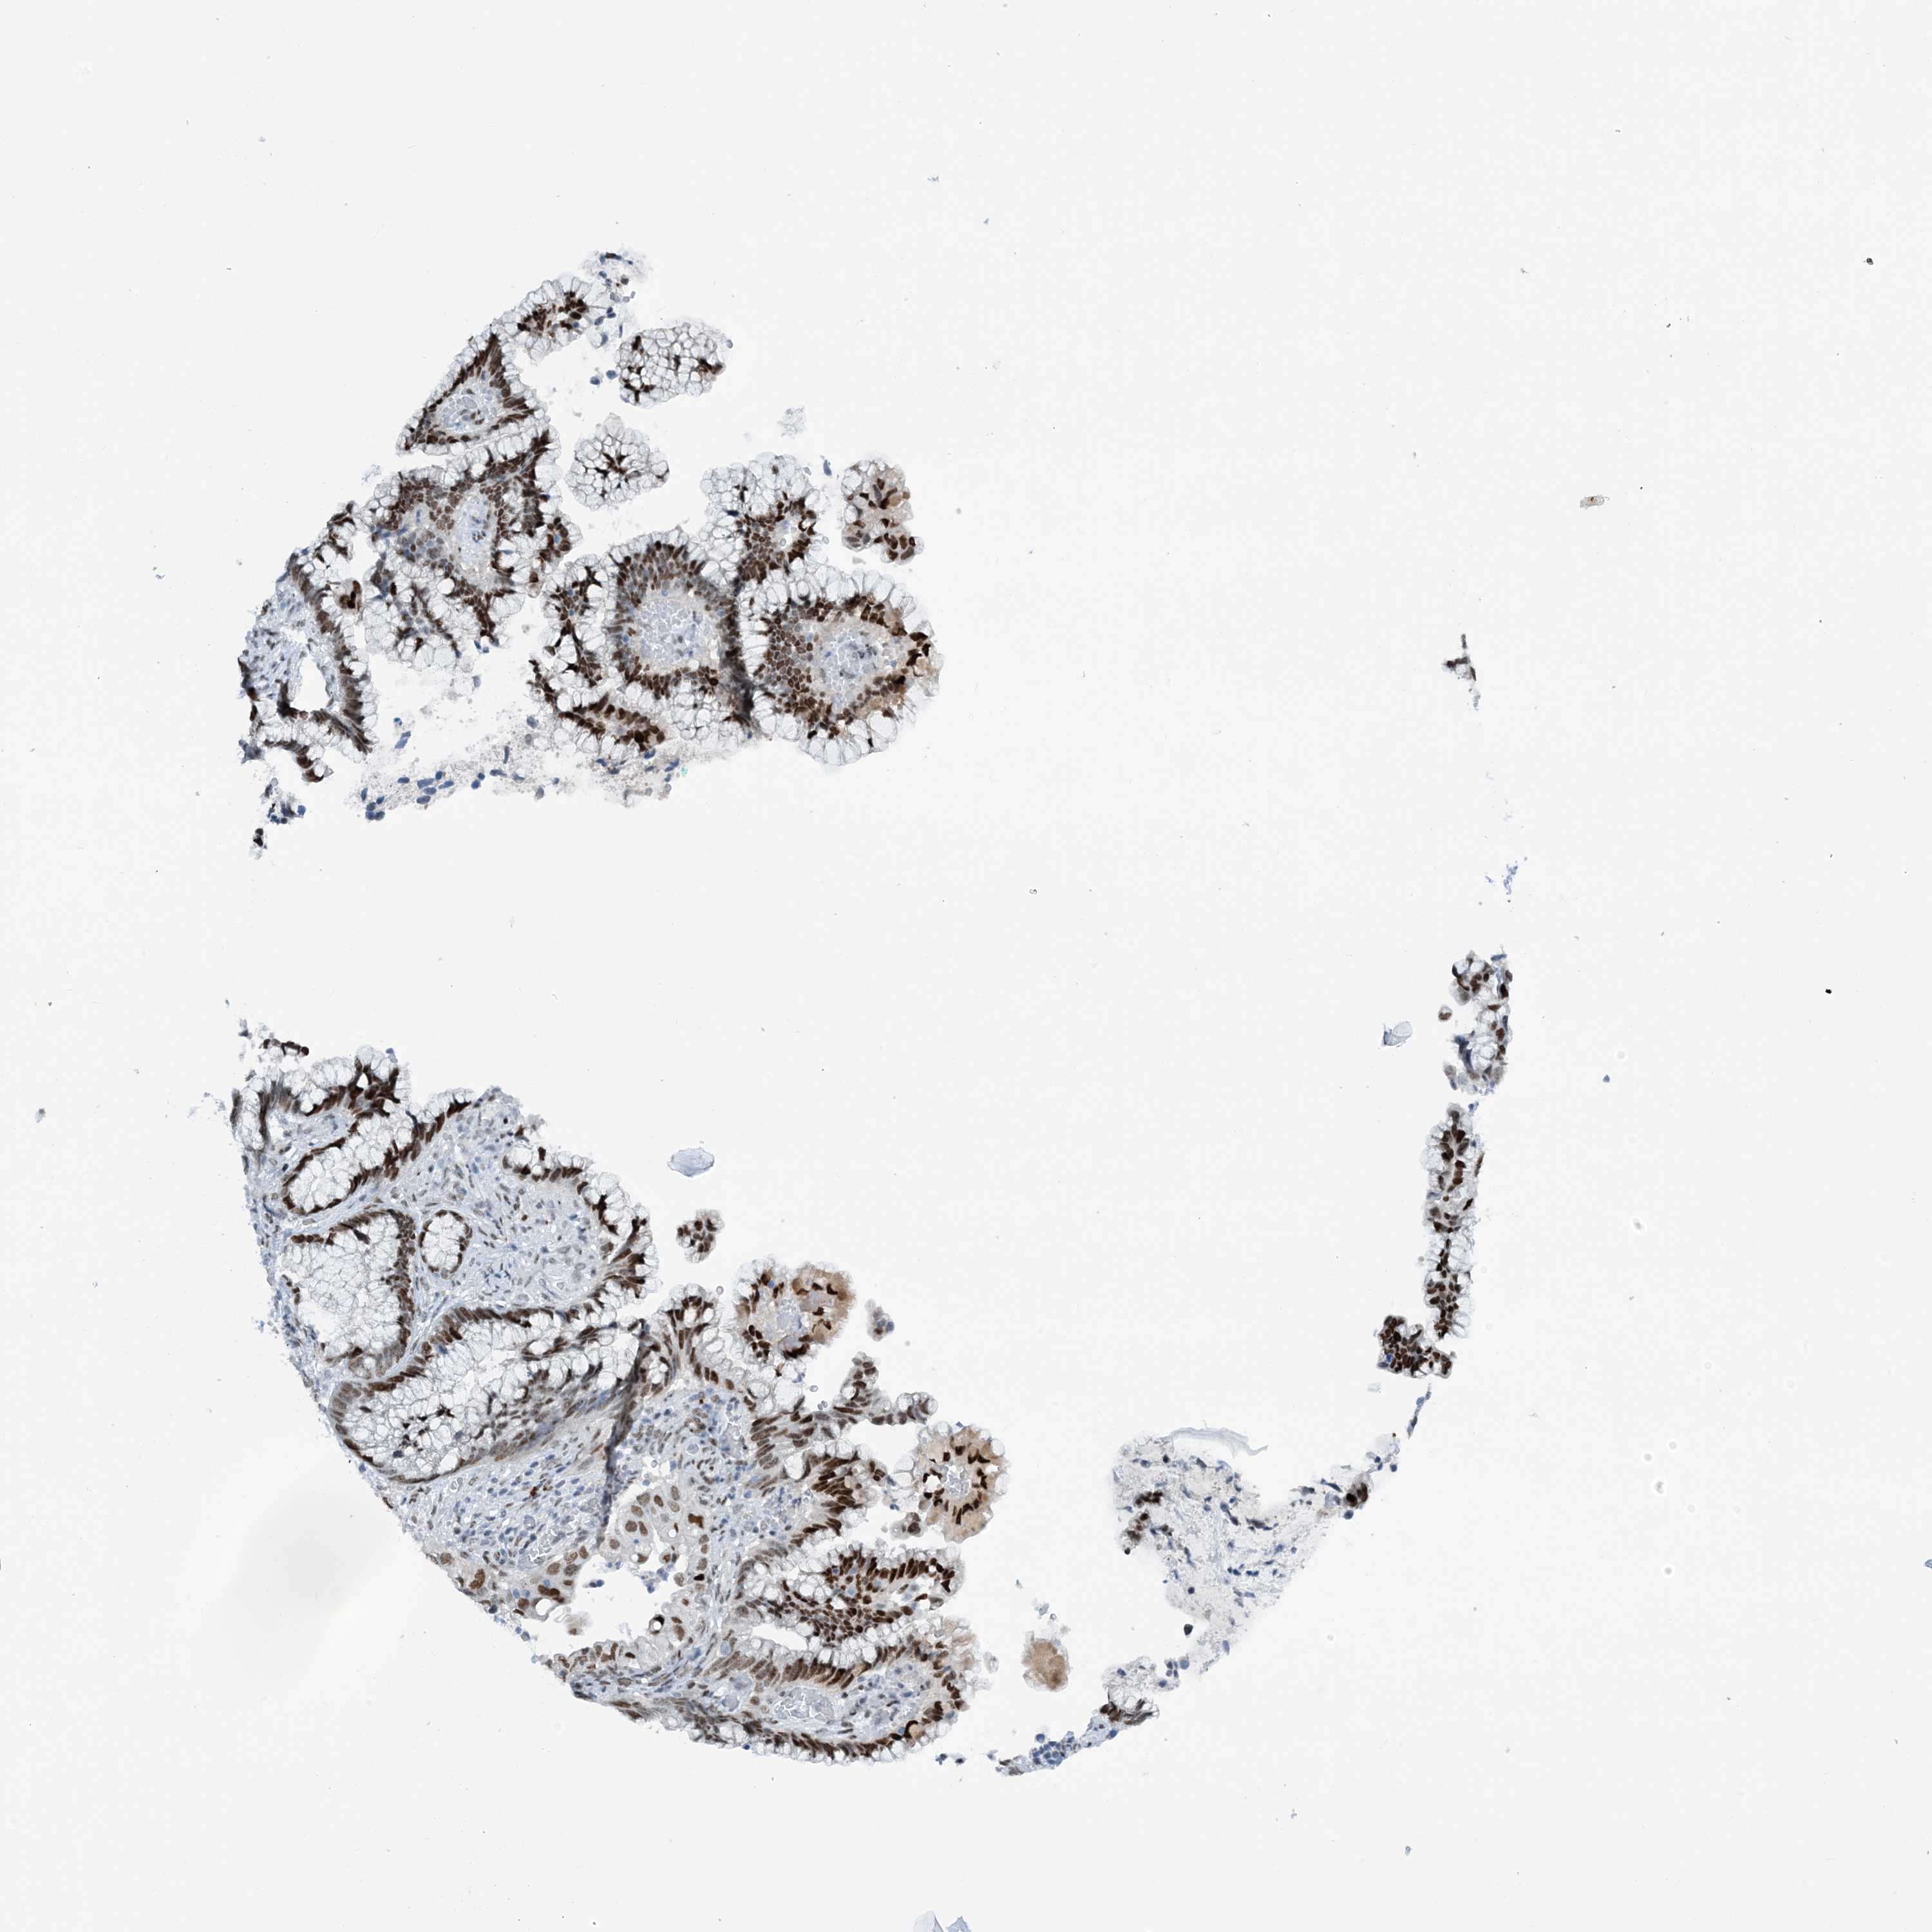

CERVICAL CANCER - Protein expressioni

A mouse-over function shows sample information and annotation data. Click on an image to view it in a full screen mode. Samples can be filtered based on level of antibody staining by selecting one or several of the following categories: high, medium, low and not detected. The assay and annotation is described here.

Note that samples used for immunohistochemistry by the Human Protein Atlas do not correspond to samples in the TCGA dataset.

Antibody stainingi

Antibody staining in the annotated cell types in the current human tissue is reported as not detected, low, medium, or high, based on conventional immunohistochemistry profiling in selected tissues. This score is based on the combination of the staining intensity and fraction of stained cells.

Each image is clickable and will lead to virtual microscopy that enables deeper exploration of all samples and also displays staining intensity scores, fraction scores and subcellular localization as well as patient and tissue information for each sample.

Antibody HPA034701

Antibody HPA034702

Staining

High

Medium

Low

Not detected

Intensity

Strong

Moderate

Weak

Negative

Quantity

>75%

75%-25%

<25%

None

Location

Nuclear

Cytoplasmic/membranous

Cytoplasmic/membranous,nuclear

Squamous cell carcinoma, NOS

Adenocarcinoma, NOS